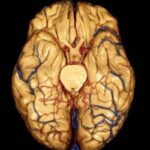

La intoxicación por bloqueadores beta-adrenérgicos es un fenómeno clínico complejo que se asocia a la administración excesiva o inadecuada de fármacos que actúan sobre los receptores beta-adrenérgicos del sistema nervioso…